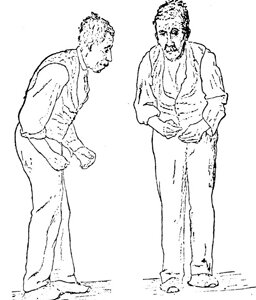

К сожалению, в мире существует немало болезней, излечить которые медики пока еще не в Далее...